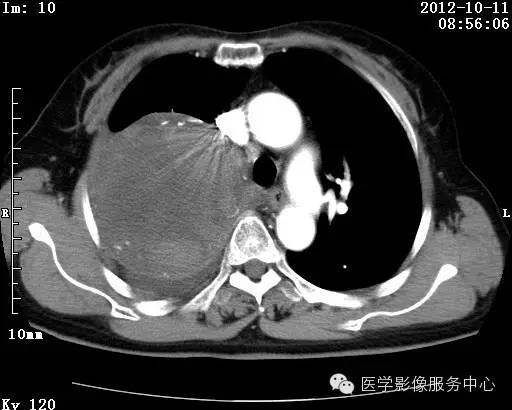

【病例】右肺巨大错构瘤1例CT影像表现

病史:女 65岁咳嗽咳痰 右肺巨大肿块就诊。

错构瘤的主要组织成分包括软骨、脂肪、平滑肌、腺体、上皮细胞,有时还有骨组织或钙化。错构瘤一般为实质致密的球形、卵圆形,也可以是分叶状或结节状,大多数直径在3cm以下。

错构瘤的发病年龄多数在40岁以上,男性多于女性。 绝大多数错构瘤(约80%以上)生长在肺的周边部,紧贴于肺的脏层胸膜之下,有时突出于肺表面。其特征钙化为爆米花样钙化,内有脂肪软骨成分等等。最常见的部位是胸膜下肺实质内,其次为主支气管或肺叶、肺段支气管内。

瘤内出现“爆米花样钙化”是诊断的主要指标之一。早期的点状、斑片状及结节状钙化 随时间增加钙化数量及范围会增加,最终可能演变 为爆米花样钙化;

另一项主要指标是瘤测得脂肪成分是诊断错构瘤。